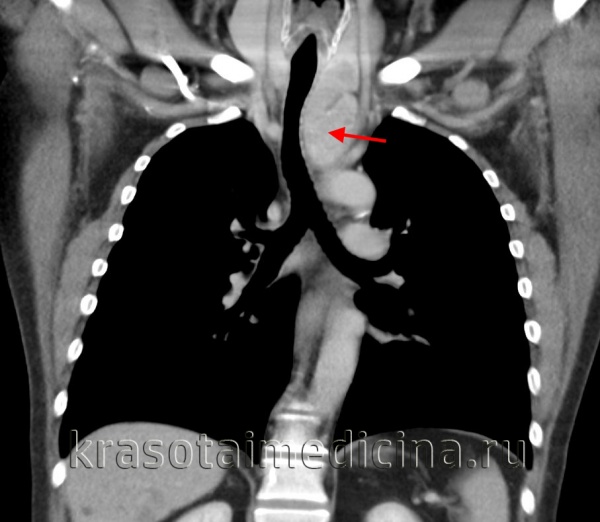

Последовательно выполненные рентгенограммы:

а — напряженный пневмомедиастинит (указан стрелками). Необычно массивное скопление в средостении;

б — успешно установленный дренаж (указан стрелкой).